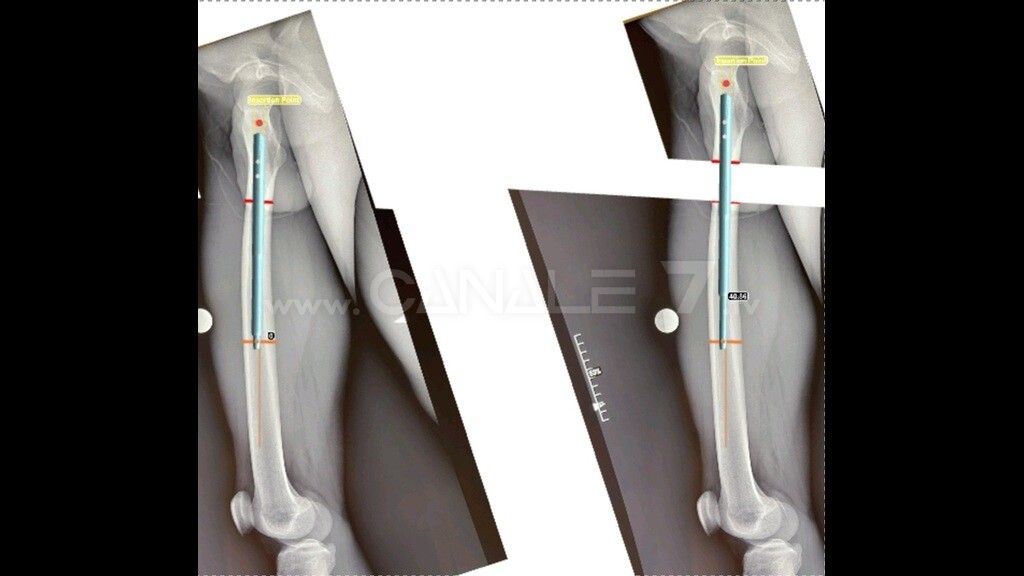

Un’operazione complessa e rara, a fronte di una diagnosi di Ipoplasia femorale congenita con una dismetria di 6 centimetri, in cui è previsto l’impiego di un chiodo endomidollare telescopico. Il dispositivo, realizzato in materiale biocompatibile, permette l’allungamento progressivo del femore di 1 millimetro al giorno e viene adoperato dal paziente stesso, in maniera del tutto autonoma, attraverso un sistema elettronico esterno che genera un segnale elettromagnetico inviato a un sensore impiantato sottocute.

In sostanza, ogni giorno il paziente azionerà direttamente una specie di “telecomando” che darà l’input al chiodo ortopedico telescopico, innescando così la crescita dell’arto. L’osteogenesi distrazionale, in virtù della rigenerazione ossea, permetterà così il recupero progressivo della dismetria in un tempo variabile, stimato in almeno due mesi in base al previsto allungamento di un millimetro al giorno, con concessione del carico completo per permettere la formazione di un callo osseo affidabile.